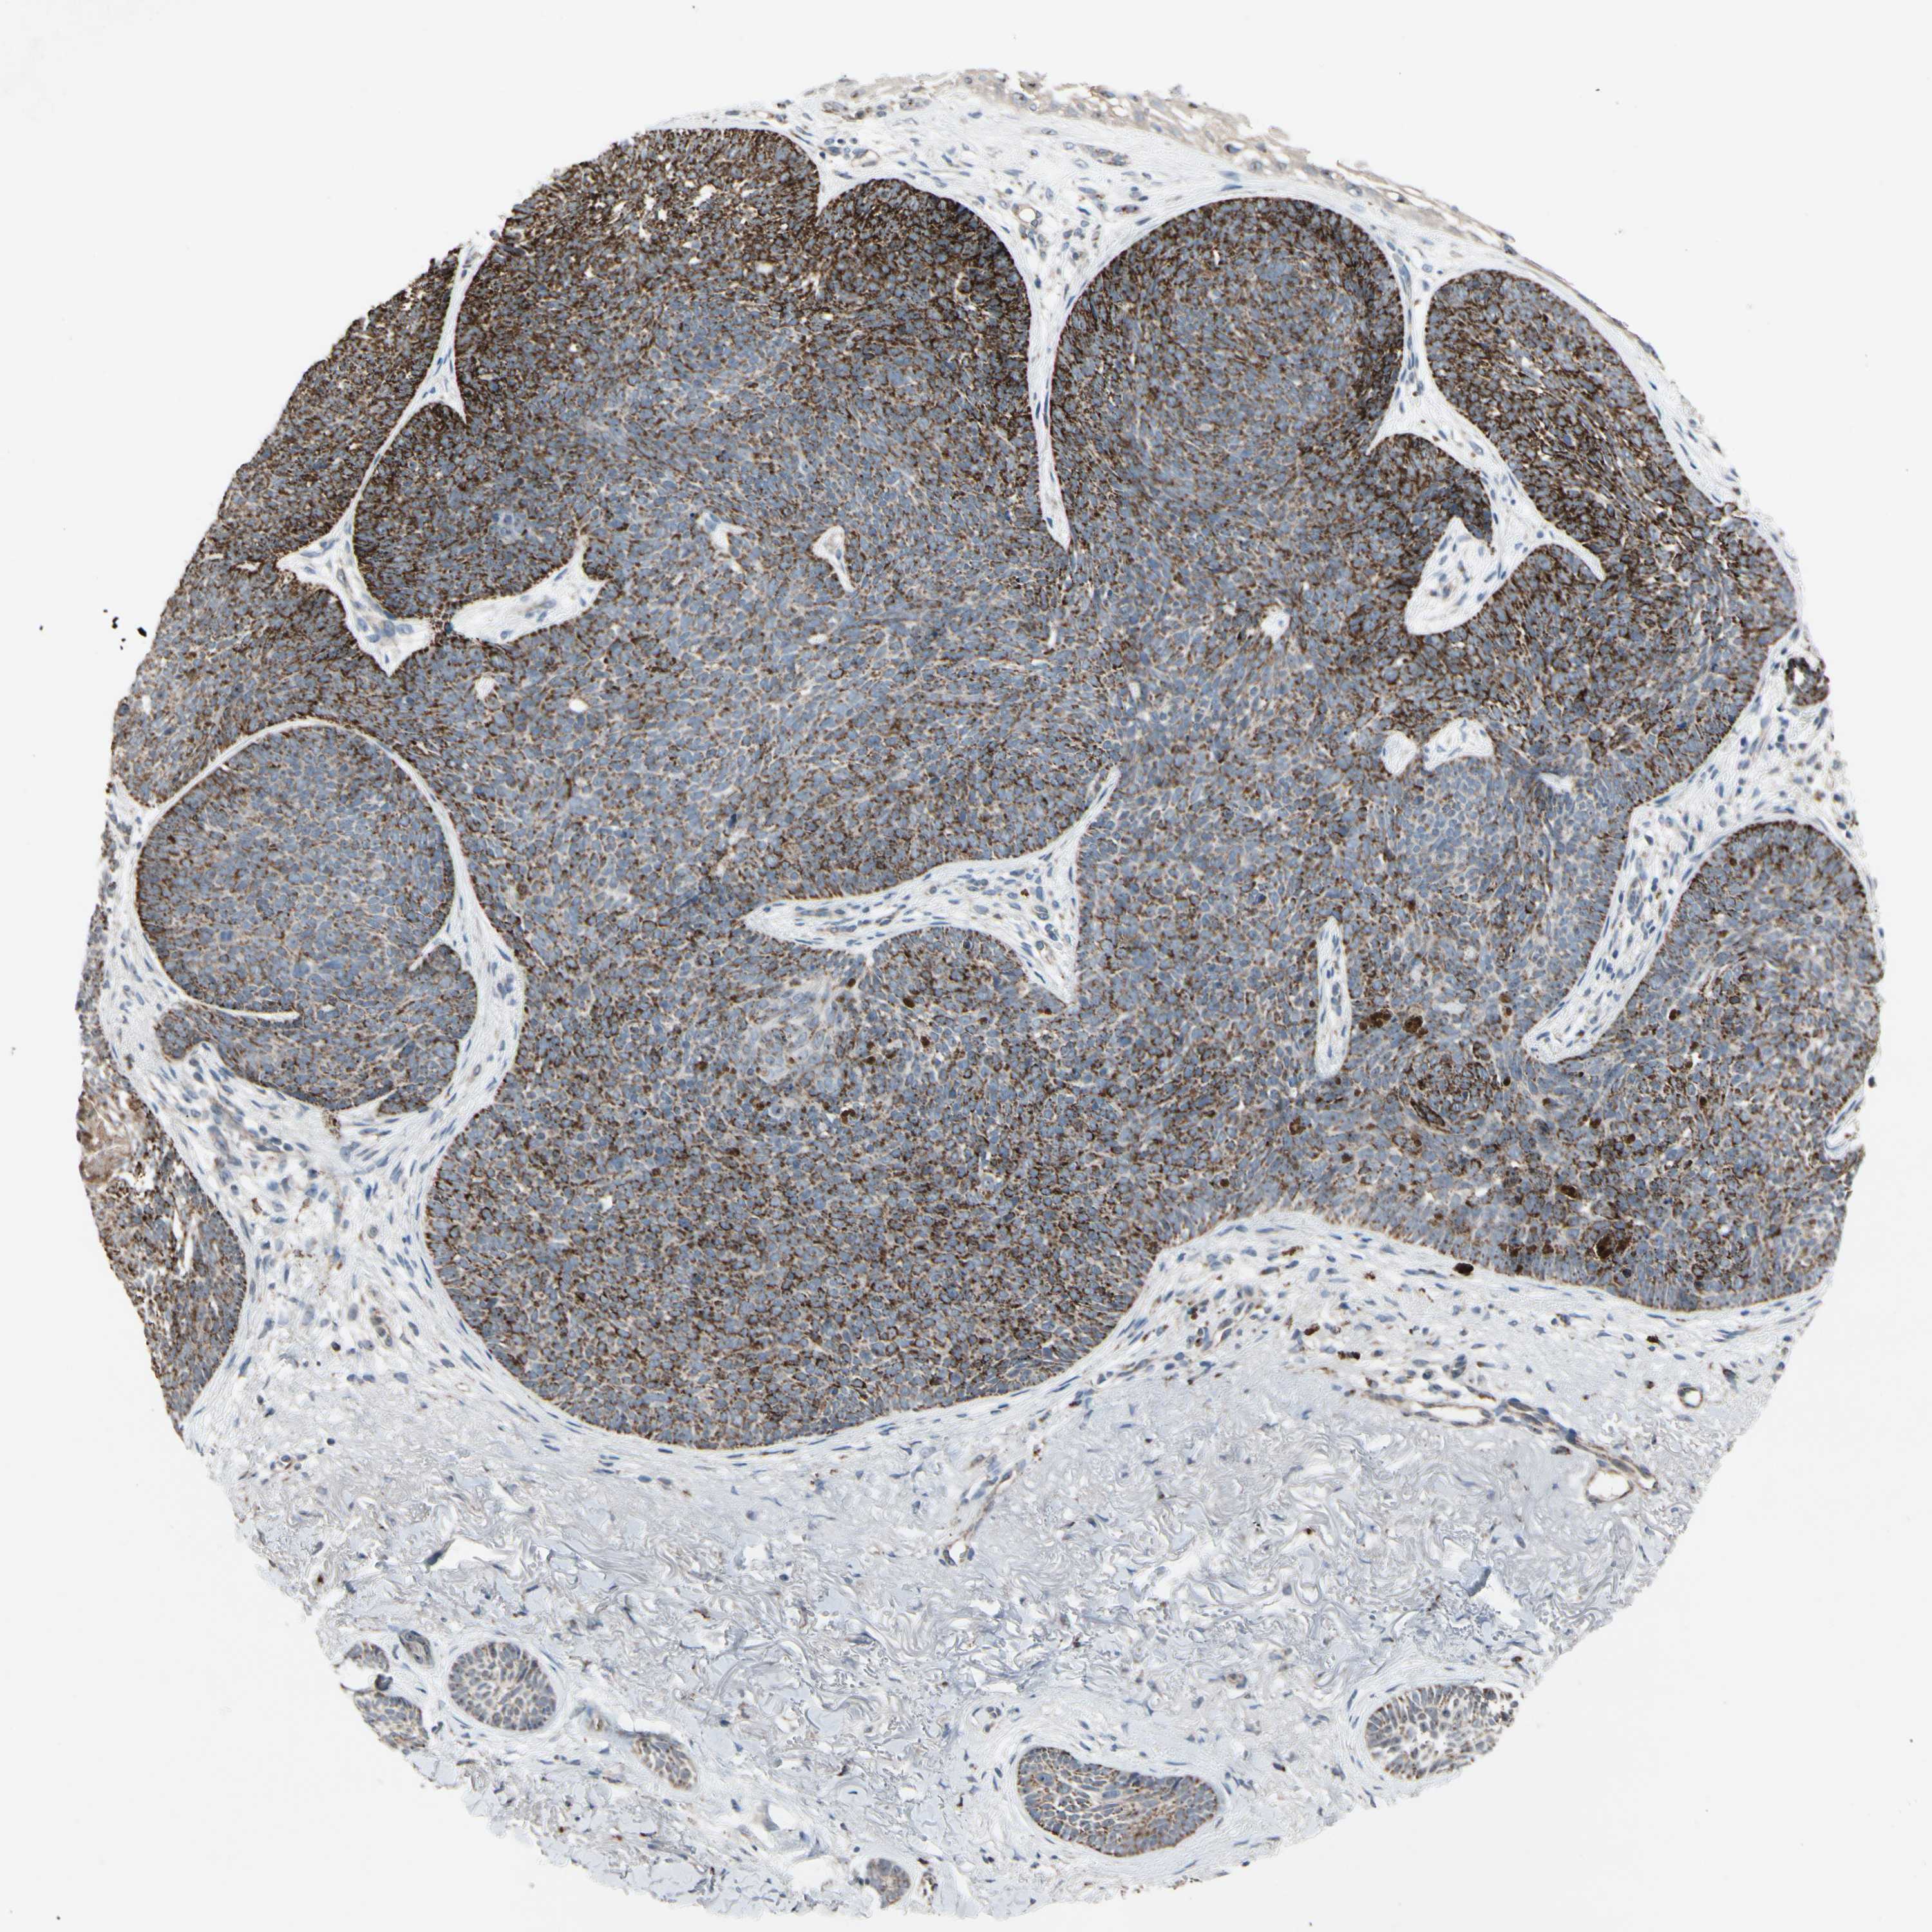

SKIN CANCER - Protein expressioni

A mouse-over function shows sample information and annotation data. Click on an image to view it in a full screen mode. Samples can be filtered based on level of antibody staining by selecting one or several of the following categories: high, medium, low and not detected. The assay and annotation is described here.

Each image is clickable and will lead to virtual microscopy that enables deeper exploration of all samples and also displays staining intensity scores, fraction scores and subcellular localization as well as patient and tissue information for each sample.

Antibody HPA008835

Staining

High

Intensity

Strong

Quantity

>75%

Location

Nuclear

Squamous cell carcinoma, NOS

Basal cell carcinoma